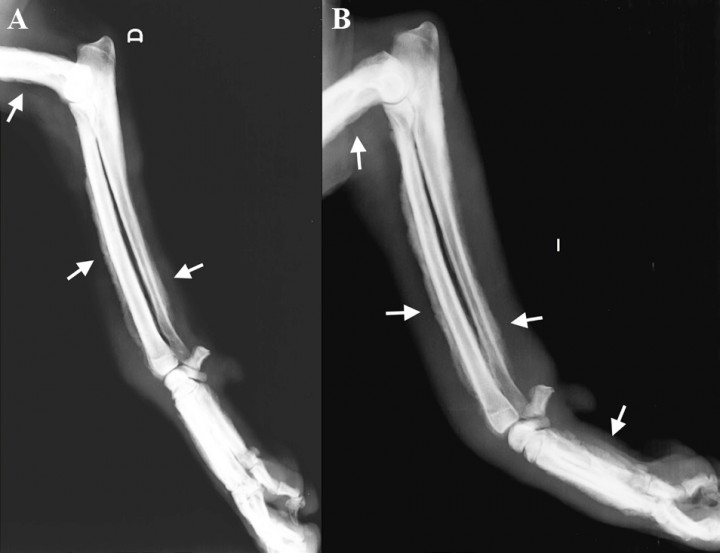

<p>Proyección dorsopalmar de la zona del carpo y metacarpo. <strong>(A)</strong> Derecha.<strong> (B) </strong>Izquierda. </p>

Proyección dorsopalmar de la zona del carpo y metacarpo. (A) Derecha. (B) Izquierda.

<p>Mismas radiografías de la Figura 1. Se observa reacción perióstica del tipo en empalizada (ver flechas) con afectación de la falange media de 2º dedo, en el aspecto lateral y medial de las falanges proximales (dedo I, II, III, IV, V), en el aspecto lateral del cuerpo del hueso metacarpiano I, II y V y del III y IV de forma más leve, y del tercio distal del cúbito y radio. No existe afectación de las superficies articulares ni destrucción ósea. Tumefacción de los tejidos blandos en la zona del carpo.</p>

Mismas radiografías de la Figura 1. Se observa reacción perióstica del tipo en empalizada (ver flechas) con afectación de la falange media de 2º dedo, en el aspecto lateral y medial de las falanges proximales (dedo I, II, III, IV, V), en el aspecto lateral del cuerpo del hueso metacarpiano I, II y V y del III y IV de forma más leve, y del tercio distal del cúbito y radio. No existe afectación de las superficies articulares ni destrucción ósea. Tumefacción de los tejidos blandos en la zona del carpo.